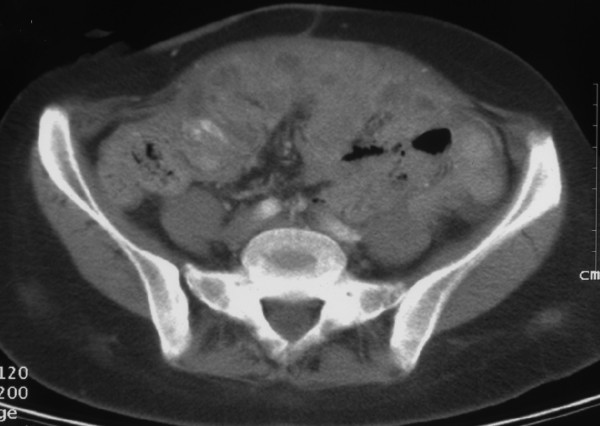

If you need a CRO to conduct an ovarian cancer clinical trial in the US, please contact us at info@sofpromed.com Are you a biotechnology or pharmaceutical company looking for a clinical research organization (CRO) partner specialized in ovarian cancer clinical trials...